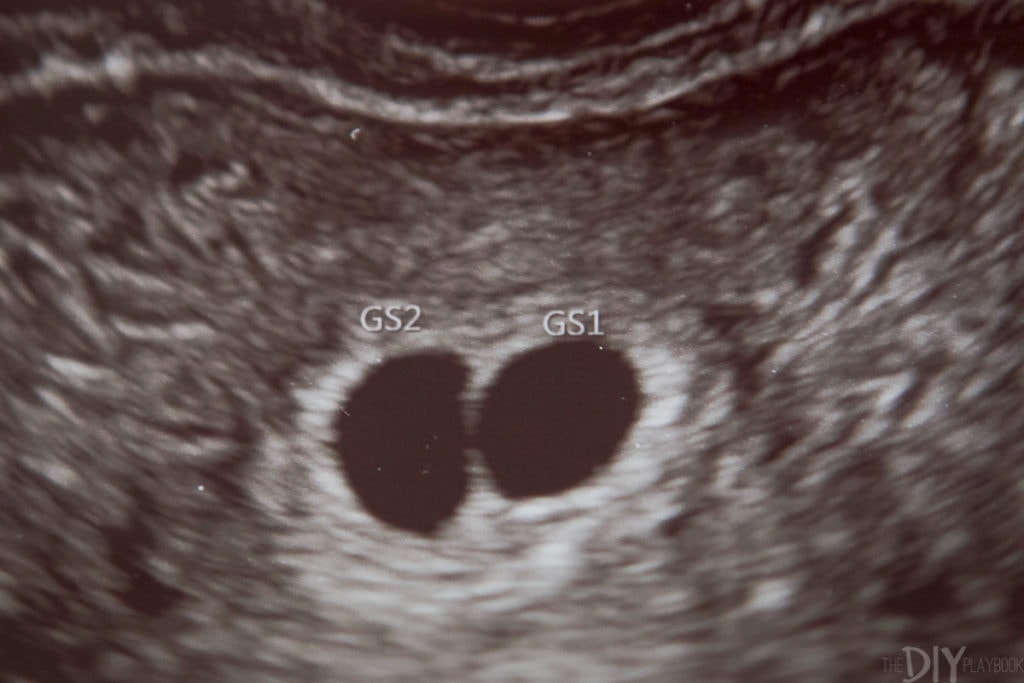

Miscarriage treatment 6 weeks | Early Miscarriage